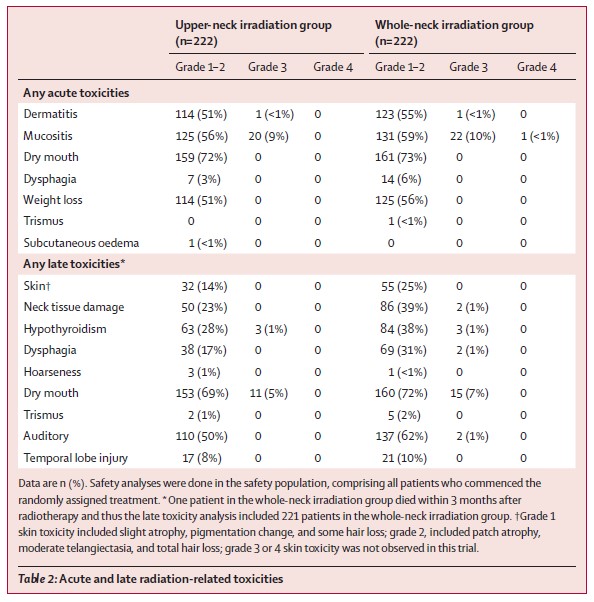

两组间的急性放射相关毒副反应相似,但上颈部照射组晚期毒性的发生率比全颈部照射组低(见下表),包括任何级别的甲状腺功能减退(30% vs 39%)、皮肤毒性(14% vs 25%)、吞咽困难(17% vs 32%)、颈部组织损伤(23% vs 40%)。

半颈照射组与全颈照射组急性毒性及远期毒性比较